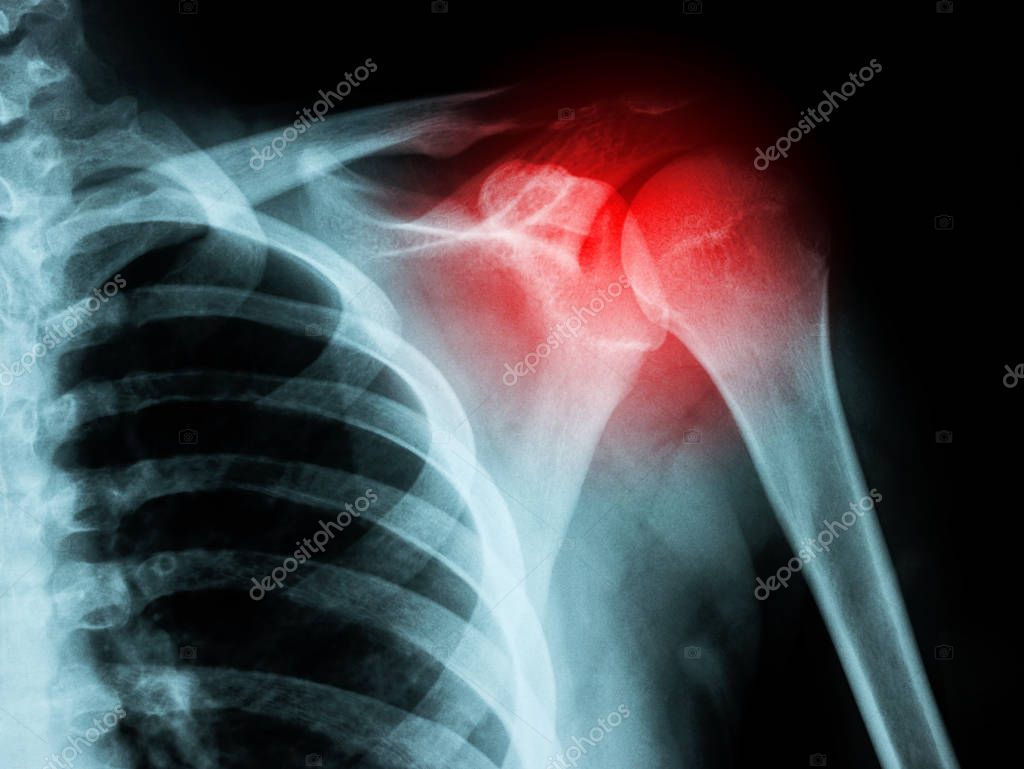

From fr.depositphotos.com

Radiographie de la fracture de l’épaule — Photographie rclassenlayouts Fracture Epaule Et Sport Consultez philippe paillard à paris 16 pour un diagnostic précis. Quels sont les symptômes d'une fracture de l'épaule? En combien de temps l'os se consolide ? Il convient simplement de prendre quelques précautions. Mais aussi toutes les autres questions spécifiques que vous vous posez. Un orthopédiste explique s’il est bon de refaire du sport après une pause forcée due à. Fracture Epaule Et Sport.